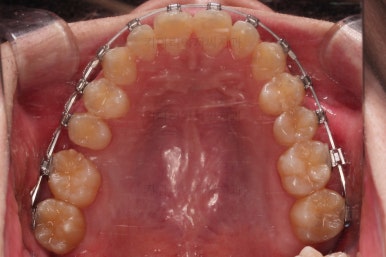

부산교정치과 초진 시 입안의 모습입니다.

앞니가 삐뚤어서 결손치아가 없었더라도 교정치료를 원하셨던 상황이었고요.

오른쪽 어금니 맞물림은 결손치아도 그렇지만 전반적인 앞뒤 차이가 있는 부정교합이 있었어요.

우선 브라켓을 부착했고요.

이번에 환자분이 선택하신 장치는 엠파워 메탈이라고 하는 자가결찰 금속장치인데요.